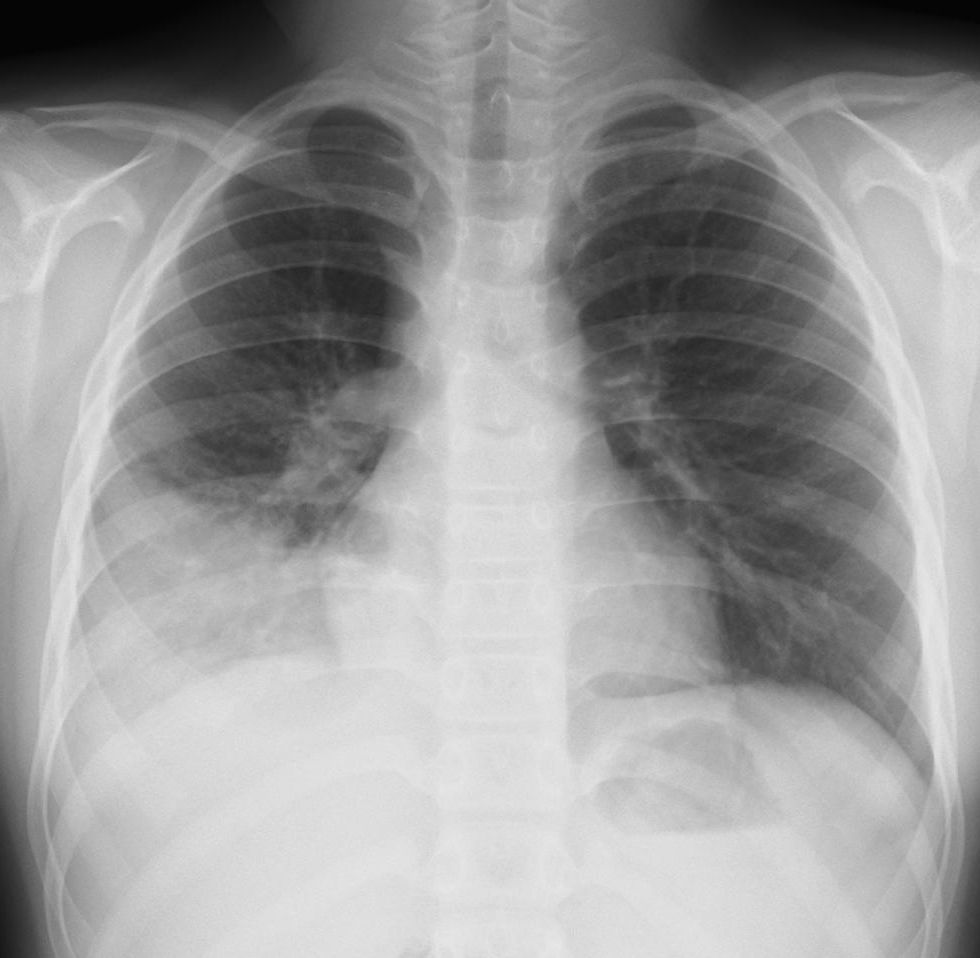

外来でよくみられる肺炎、マイコ・クラミジア・肺炎球菌・ウイルス(RSウイルス・hMPV・インフルエンザウイルスA・B)について実際に経験、外来で治癒した症例を提示します。軽症な変化のものが大多数ですが中には重症なものも紛れていて、注意が必要になります。

【マイコプラズマ肺炎】